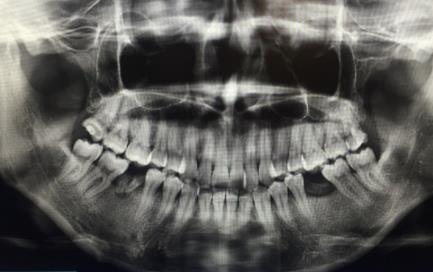

智齒牽引前

一般來說,智齒牽引有幾種情況,比如第六磨牙脫落了,把第七磨牙牽引到地六磨牙的位置,然後把智齒牽引到第七磨牙的位置,這樣一來的話,就不用拔除智齒,也不用在正畸後需要種植第六磨牙了。

臨(lin) 床上,這兩(liang) 種智齒牽引方式都有成功**,但是,並不一定適合每個(ge) 人,而且智齒牽引也不一定都能成功,醫生也不能保障完全成功,隻能說是盡量把智齒利用起來,具體(ti) 每個(ge) 人做智齒牽引的成功率通常還需要找正畸醫生詳細谘詢。